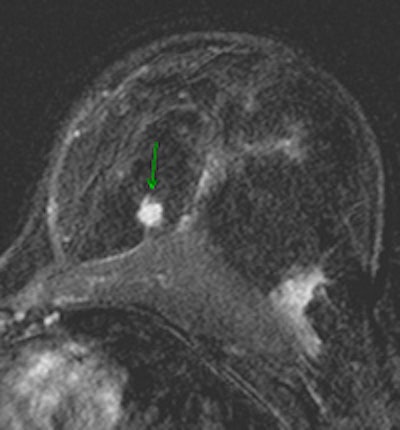

![]() |

| Contrast-enhanced breast MRI (subtracted image three minutes after contrast medium injection). Patient with a diagnosis of invasive ductal carcinoma (ultrasound-guided biopsies). At surgery, no cancer was found. Ultrasound examination after surgery was unable to detect the lesion. At MRI, the lesion was well depicted (inner quadrants, deep location). Image courtesy of Dr. Anne Tardivon. |